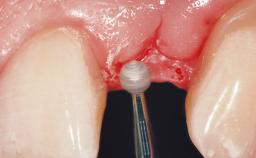

A 56-year-old female patient was referred to the clinic for the functional rehabilitation of her left mandible. The healthy, non-smoking patient presented with loss of retention of crown 35 due to secondary root caries. In addition, she had a single-tooth gap at site 36 with clearly discernible facial atrophy. The panoramic radiograph exhibited crowned teeth 35 and 37, both with a root canal filling. Tooth 37 showed a radiolucent area on the mesial aspect. Tooth 38 did not show any signs of pathology. Based on the clinical and radiographic findings, it was decided to remove root 35 and tooth 37, creating an extended edentulous space with three missing teeth. As requested by the patient, tooth 38 was left in place. The removal of both teeth was done without major flap elevation. The wound margins at site 35 had to be slightly elevated to remove the root remnant.

Bone Augmentation Horizontal|Simultaneous

Augmentation Materials Autogenous chips|Xenogenous|Membrane